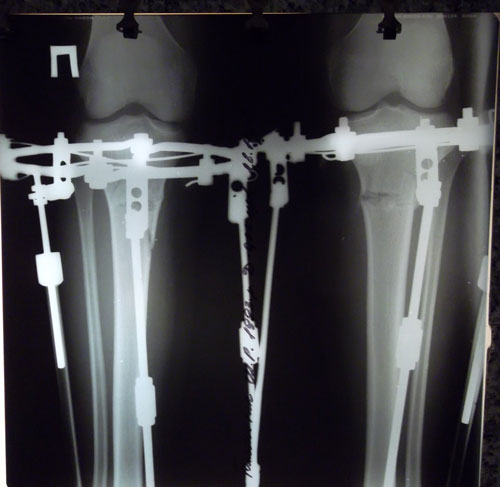

Дата операции 03.11.2015г.

Дата снятия 08.01.2016г.

Срок лечения 65 дней.